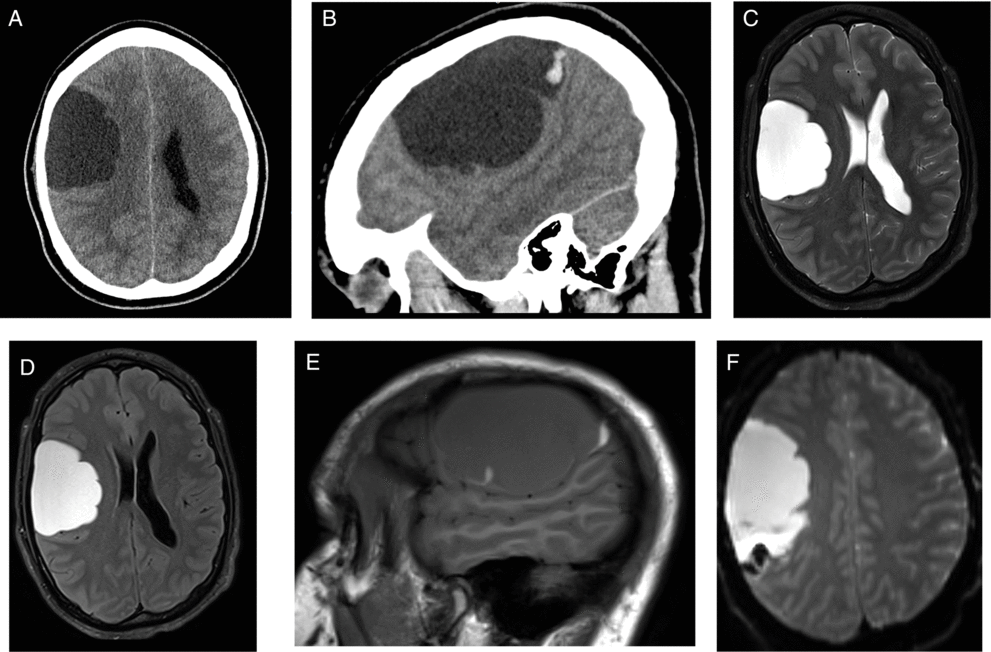

This is a case of a 30-year-old right-handed male patient who presented to the hospital in 2014 after hitting his head on the mat during a wrestling match followed by headache and temporary peripheral vision limitation. The patient’s past medical history was unremarkable. On physical examination, Glasgow Coma Scale was 15 with no focal neurological deficits. Unenhanced head computed tomography (CT) and enhanced brain magnetic resonance imaging (MRI) were performed (Figure 1). The patient was managed conservatively, and follow-up CT and MRI in 2015 (Figure 2) demonstrated significant decrease in size of the previously seen right frontoparietal lesion with also changes in its radiological features. The patient remained asymptomatic for about 3 years when in 2018 he presented to the Emergency Department with increasing headaches and peripheral vision loss. MRI demonstrated an increase in the right frontal lesion size (Figure 3). He underwent surgical resection of the lesion.

Figure 1: Unenhanced computed tomography (CT) axial (A) and sagittal (B) performed in 2014 revealed a large extra-axial frontoparietal lobulated cystic mass. Magnetic resonance imaging (MRI) axial T2-weighted image (C) showed hyperintense cystic lesion causing mass effect over the brain parenchyma. On fluid-attenuated inversion recovery (FLAIR) (D), the lesion presented higher signal in relation to the cerebrospinal fluid (CSF). Sagittal T1-weighted image (E) showed isointense central content with a focus of hyperintensity in the posterior aspect of the cystic mass. Gradient echo (GRE) images (F) showed blooming artifacts confirming the presence of blood products. No abnormal enhancement or restricted diffusion was seen (not shown).